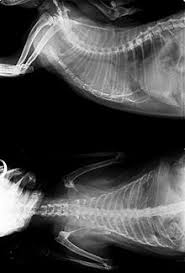

How Did My Cat Get Lung Cancer : Cancer In Cats Elwood Vet : Lung cancer survivors may get too many pet scans.. The same drugs used to treat human cancer patients are used in cats too, only in smaller doses. I spent about 3 hours researching on the. Squamous cell carcinoma and bronchioalveolar carcinoma are other types of cancer that occur in cat lungs. While cancer in cats is not as common as it in dogs, it is still one of the leading causes of death in older cats. Causes of lung cancer a clear cause for lung cancer hasn't been discovered yet.

This type of carcinoma is relatively rare in cats, with no known breed disposition. The commonest types of cancer affect the white blood cells, the skin and the breast. Probably $500 to $1,000 to do the initial diagnostic testing. With the advent of virus testing, vaccination against felv and selective breeding, the cancer caused by this virus has diminished greatly. The clinical signs of lung cancer can vary. As i mentioned, the virus felv can cause cancer in cats. Lung cancer in felines can be primary, when the cancerous tissues have developed in the lung area first, or secondary, when the disease has spread from another part of the body. (that and the blood work showed no increase/decrease in wbc count) the vet feels certain it is cancer and referred me to a specialist for a definitive diagnosis. Primary lung tumors and metastatic lung tumors. Best no dust cat litter. Lymphoma is by and large the most common cancer that affects cats, although there are other types of feline cancers that can affect domestic cats. Adenocarcinoma grows rapidly and metastasizes to distant parts of the body and organs, including the brain, eyes, bones, and lymph nodes. The number of cases of primary lung tumors in cats has increased in recent years, though the exact reason for the increase is unknown.

Lung Cancer In Cats Cat World from cat-world.com Your vet will do a complete physical exam and blood work and might. Chemotherapy is useful in treating types of cancer that affect the whole body, including lymphoma. Vets don't know what causes cat lung cancer, but they think pollution might be a causal factor. Of all the species, cats tolerate chemotherapy the best.. The number of cases of primary lung tumors in cats has increased in recent years, though the exact reason for the increase is unknown. I spent about 3 hours researching on the. Primary lung cancer originates in the lungs, while secondary lung cancer spreads to the lungs from some other part of the body. Probably $500 to $1,000 to do the initial diagnostic testing.

The most common primary lung tumour in cats is pulmonary adenocarcinoma, which can arise from the bronchus (the tubes that carry air into the lungs) or from the alveolae (the air sacs). Prices at a general veterinary practice may be much less. The number of cases of primary lung tumors in cats has increased in recent years, though the exact reason for the increase is unknown. Only about two thirds of dogs and cats actually exhibit clinical signs. Cat lung cancer can be one of two types, either primary or secondary.